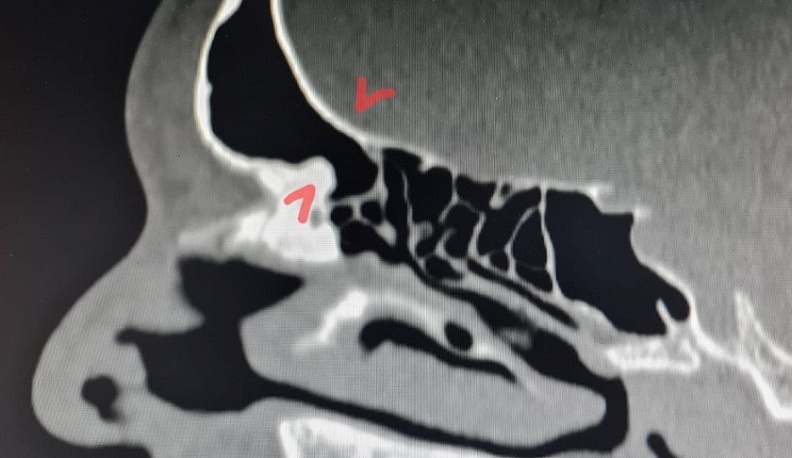

Фото: Елена Разумеева/Вконтакте. На снимке пазуха с блокированными путями оттока.